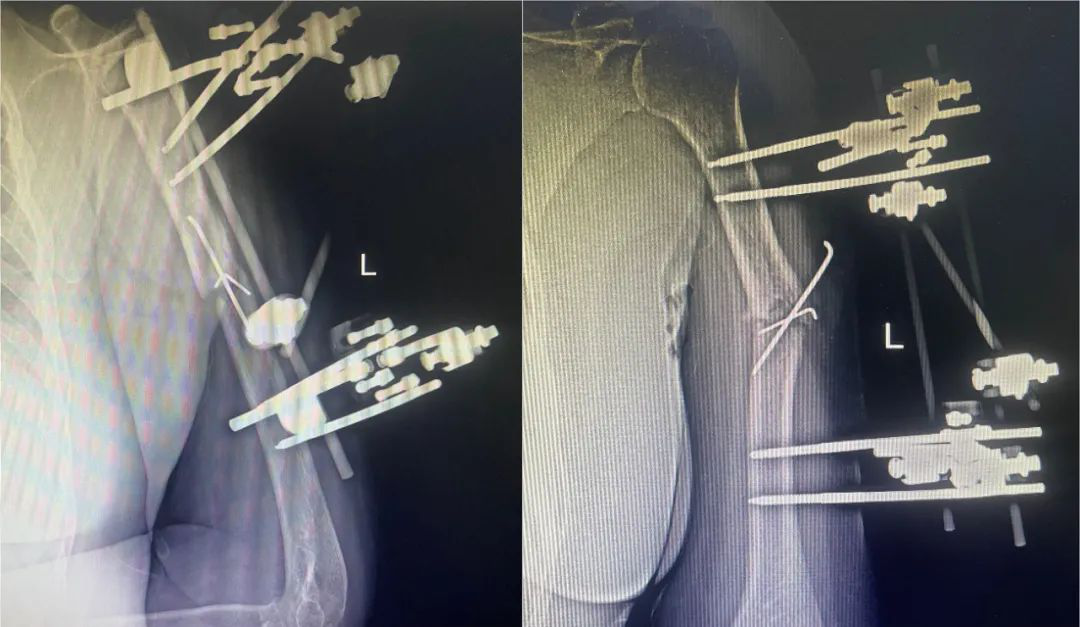

外固定架

下一页 骨科外固定架支架应用